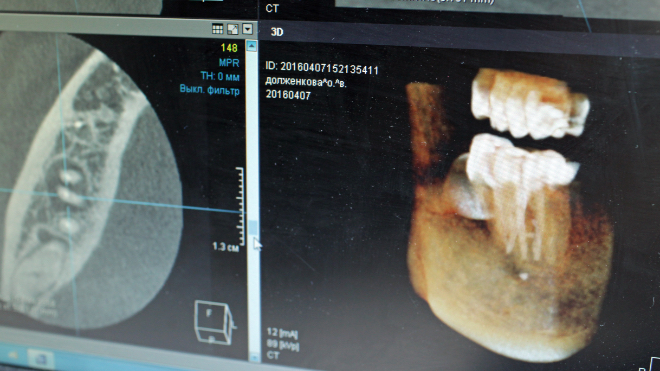

В городской поликлинике Гатчины поставили новый рентген-аппарат. Он создает снимки сразу в трех положениях: сидя, лежа и стоя.

Высокоточная диагностическая установка «УНИЭКСПЕРТ 2 плюс» предназначена для рентгенологического исследования органов грудной клетки, позвоночника, суставов, кисти, черепа и мягких тканей — Александр Жарков, глава Комитета по здравоохранению Ленинградской области.